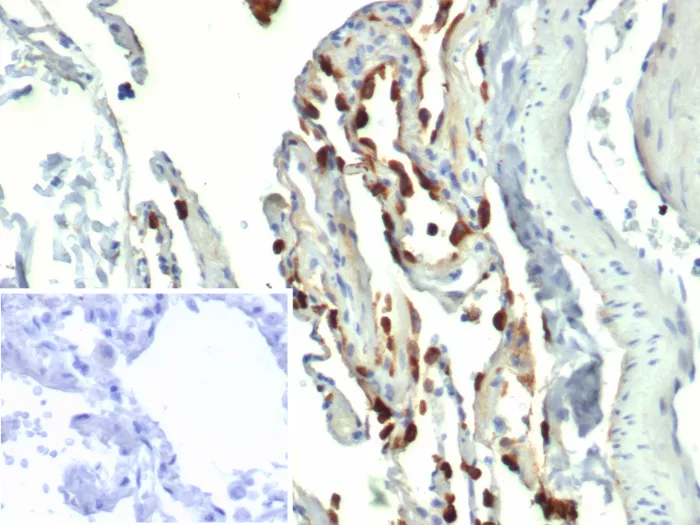

Formalin-fixed, paraffin-embedded human lung stained with Surfactant Protein D Mouse Monoclonal Antibody (SFTPD/4362). Inset: PBS instead of primary antibody; secondary only negative control.